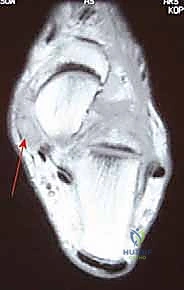

* التصوير بالرنين المغناطيسي (MRI): هو الأداة الأدق لتقييم حالة الأنسجة الرخوة. يوضح الرنين المغناطيسي درجة تمزق وتر الظنبوب الخلفي، وحالة الأربطة الداعمة (الرباط الزنبركي والدالي)، ووجود أي التهابات أو ارتشاح في نخاع العظم.